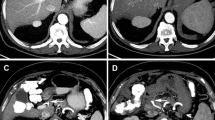

Of 133 patients who received a workup for RE with MDCT and DSA, 19 (14 %) were excluded for the following reasons: previous extensive liver surgery (n = 12), severe liver cirrhosis distorting the liver anatomy (n = 4), or large tumor mass distorting the liver anatomy (n = 3). The hepatic arterial configuration and arterial segmental vascularization of the remaining patients were assessed (Fig. 1). However, in four patients (4 %), the arterial segmental vascularization could not be assessed reliably on MDCT, due to the very small caliber of the arterial branches. Consequently, we present the results of the hepatic arterial configuration and arterial segmental vascularization of the remaining 110 patients.

The hepatic arterial segmental vascularization patterns are summarized in Table 4 and schematically illustrated in Figs. 2, 3, 4, 5 and 6. An example of DSA and multiplanar MDCT images of the hepatic arterial segmental vascularization pattern is shown in Fig. 7 for a patient with an rRHA originating from the SMA.

DSA (A–B) and multiplanar MDCT (C–F) images of the hepatic arterial segmental vascularization pattern in a patient with an rRHA originating from the SMA. A Superior mesenteric arteriogram shows a replaced right hepatic artery (white arrowhead) originating from the SMA. B DSA obtained from the CHA. The CHA divides into GDA and LHA (black asterisk). The LHA first gives of a branch to S2 (black arrowhead), and bifurcates more distally into a branch to S3 (white arrow) and S4 (black arrow). C–D Corresponding arterial phase coronal MIP images. E–F Corresponding arterial phase axial MIP images. Note the retroportal course of the rRHA (white arrowhead), and the perfect intrahepatic coordination between distal portal and arterial branches